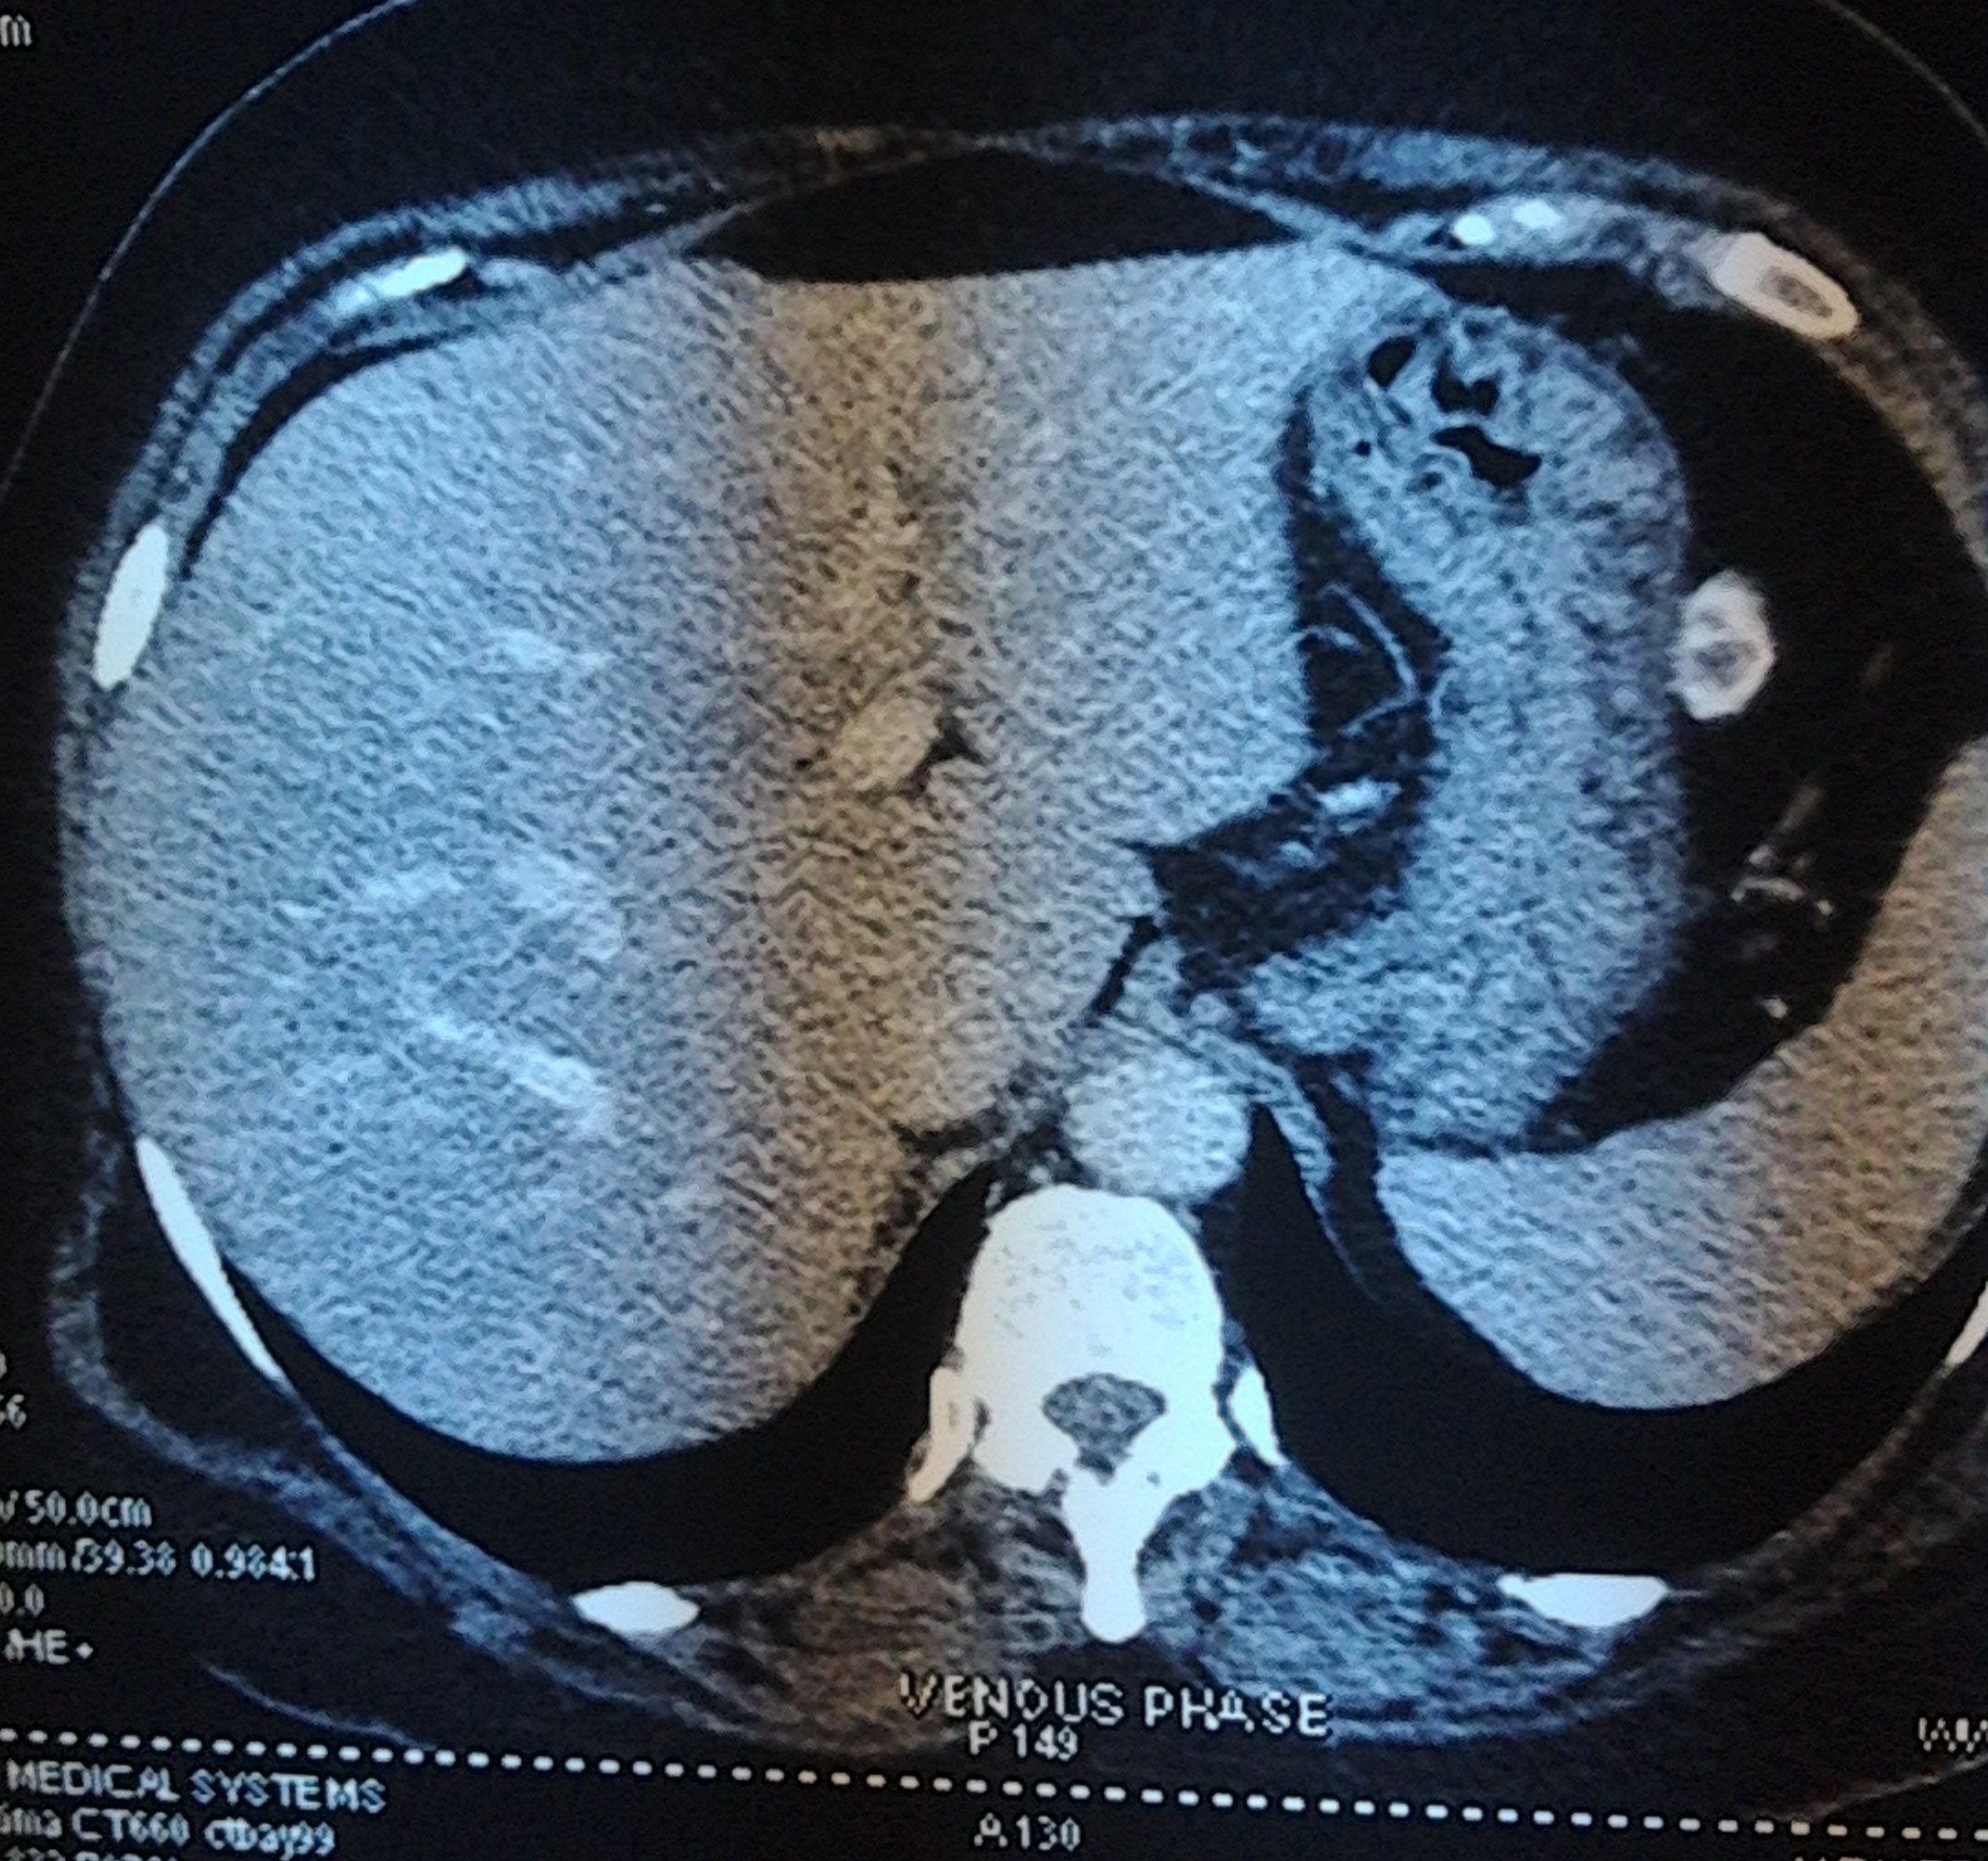

So a CT scan was done next . These pictures are reproduced here using a cell phone’s camera.

The following picture shows the enlarged uterus and large sub serous myomas extending upto the liver.

The next picture shows the adenomyosis

The large sub serous fibroids are seen below.

The liver is shown below.